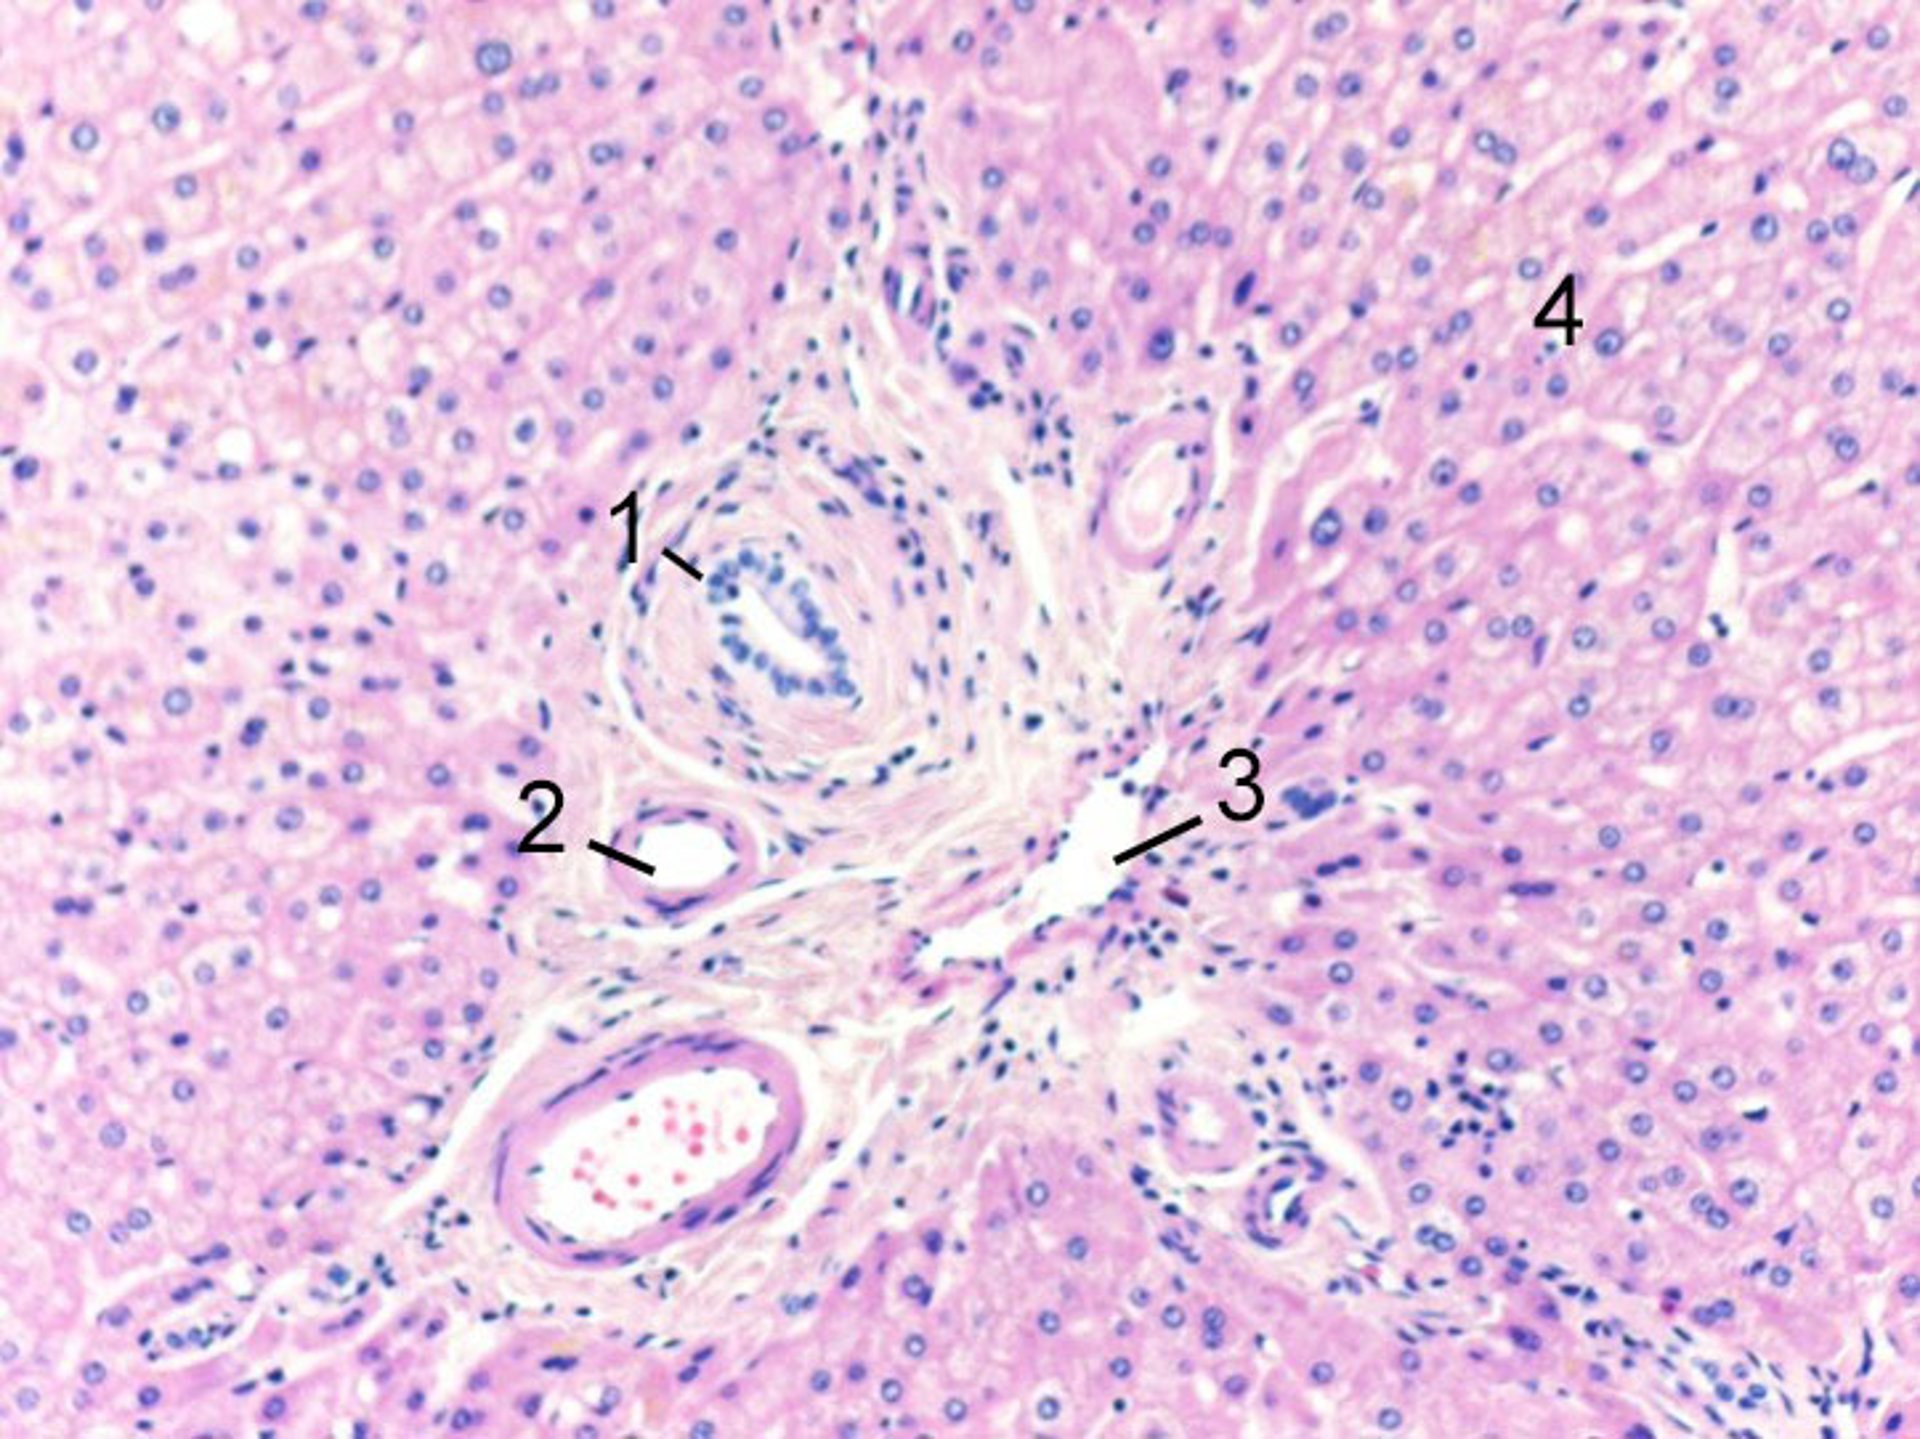

Normal Portal Triad

1 = Bile duct branch; 2 = hepatic artery branch; 3 = portal vein branch; 4 = hepatocytes.

Image courtesy of Danielle Tholey, MD, and M. Isabel Fiel, MD, MS, FAASLD.